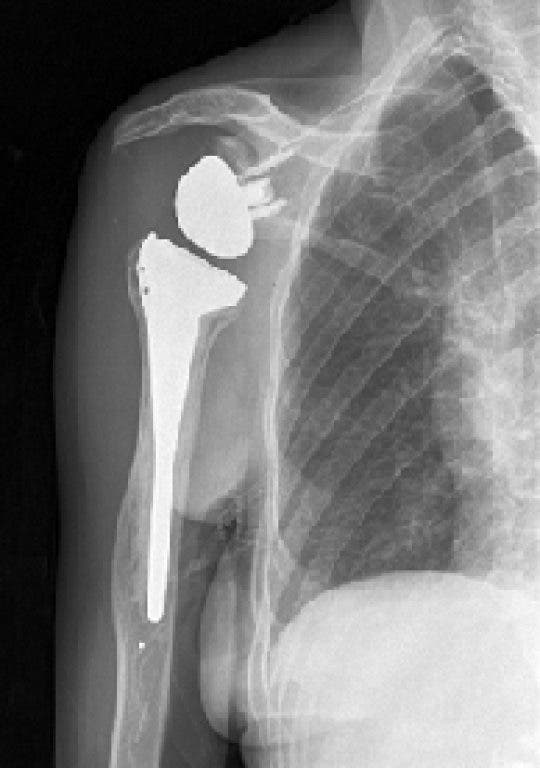

Unlike a conventional total shoulder replacement in which the joint surfaces are replaced with a plastic socket attached to the shoulder bone and a metal ball with a stem is attached to the upper arm, reverse total shoulder replacement surgery actually reverses the anatomy of the shoulder.

By reversing the shoulder’s normal anatomy, the deltoid muscle, one of the stronger shoulder muscles, is given control to raise the arm. The socket and metal ball are switched with the metal ball attached to the shoulder bone and a plastic socket attached to the upper arm bone.